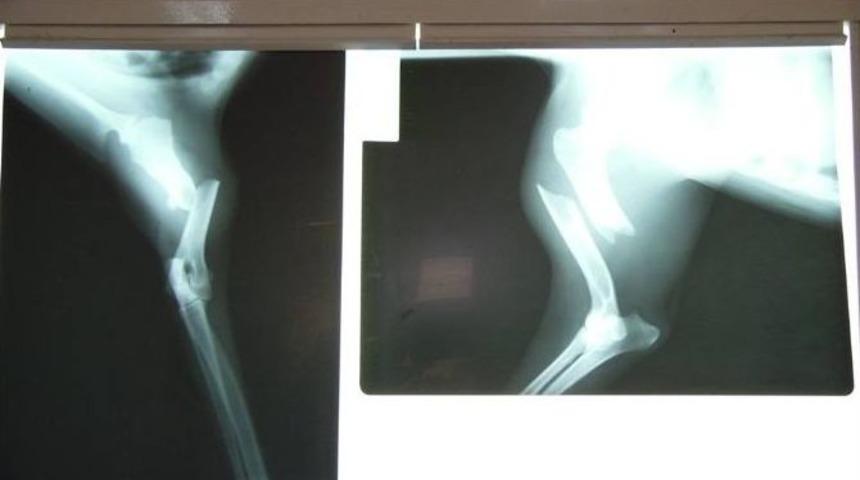

Bursa’nın İnegöl ilçesinde, bir aracın çarpıp kaçtığı sokak köpeği, vatandaşlar sayesinde hayata tutundu. Yaralı köpek, İnegöl Belediyesi Veteriner İşleri Müdürlüğü’ndeki ilk müdahalesinin ardından Nilüfer Belediyesi Veteriner İşleri Müdürlüğü’nde ameliyat edilerek sağlığına kavuşturuldu.Edinilen bilgiye göre, kara yolandan geçen sokak köpeğine bir araç çarptı. Sürücü durmayıp yoluna devam etti. Yol kenarında can çekişen 5 yaşındaki sokak köpeği, vatandaşlar tarafından fark edilerek İnegöl Belediye Veteriner İşleri Müdürlüğü’ne götürüldü. Burada ilk müdahalesi yapılan talihsiz sokak köpeği, ardından Nilüfer Belediyesi Veteriner İşleri Müdürlüğü’ne sevk edildi. Burada tahlilleri yapılan köpeğin sağ ön ayağında kırık olduğu tespit edildi. Hemen ameliyata alınan köpek, kırık olan ayağına platin takılarak tedavi edildi.Operasyonu gerçekleştiren Op. Dr. Ayşe Yazıcı, “Müdürlüğümüze getirilen köpeğin yapılan radyografik muayenesinde humerus kemiğinde diafizer kırık olduğunu tespit ettik. İnegöl Belediyesi veteriner hekimleri ile birlikte yaptığımız operasyonda intramedullar pin fikzasyon tekniğiyle başarılı bir operasyon gerçekleştirdik. Fizik tedavi sonrasında yeniden bacağını kullanacak. Operasyonun ardından İnegöl Belediyesi yetkililerine teslim edilen köpeğimizin yeniden sağlığına kavuşması ve bir canı daha hayata döndürmenin mutluluğu içerisindeyiz" dedi.